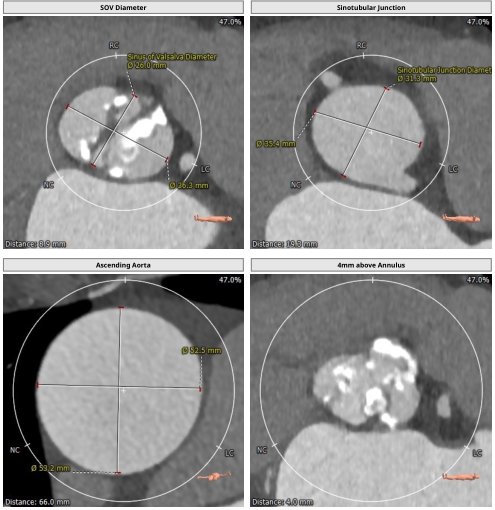

TYPE0型二叶式主动脉瓣,瓣叶严重钙化增厚。冠脉无明显狭窄,冠脉开口高度左侧15.4mm、右侧14.9mm,冠状窦水平无瓣叶,TAVR手术冠脉闭塞风险低。升主动脉扩张,主动脉扭曲。双侧股动脉通畅,无明显钙化。

瓣膜选择:基于术前CTA的测量结果,因二叶瓣严重钙化为降低瓣环破裂等风险选择偏小一号的人工瓣膜(downsize策略)植入23 mm SAPIEN 3瓣膜。

二叶瓣主动脉瓣狭窄解剖结构较为特殊,常合并主动脉瓣钙化、主动脉扩张等病变,导致TAVR术后易发生瓣周漏、瓣膜移位、瓣环破裂等多种并发症,TAVR操作具有一定挑战性。瓣膜尺寸选择及精确定位预防瓣膜发生滑脱方面需要认真考虑。二叶瓣瓣叶开口形态变化及瓣叶严重钙化使得实际瓣叶开口径通常小于瓣环径,瓣膜尺寸选择有时采用偏小型号(downsize策略),术前CT测量评估及术中球囊预扩张均可为瓣膜选择提供重要参考信息。尽管我们选取了偏小一号的23 mm SAPIEN 3瓣膜,在球囊预扩张及瓣膜植入过程中仍可以观察到钙化团块明显移位,如按照常规选择植入26 mm SAPIEN 3瓣膜会使瓣膜滑脱、瓣膜破裂等风险增加。该患者升主动脉明显增宽,会导致输送系统过弓后向大弯侧移位,再加上主动脉瓣钙化严重,从而进一步增加了跨瓣的难度,SAPIEN 3瓣膜经导管主动脉瓣瓣膜输送系统具有双重调弯功能,可调节远端辅助通过复杂的解剖结构,降低主动脉损伤的风险,并有助于瓣膜定位过程中控制同轴性,精细控制定位,确保精准放置人工瓣膜。术后患者恢复良好,胸闷、气喘症状消失,心功能明显改善,顺利出院。